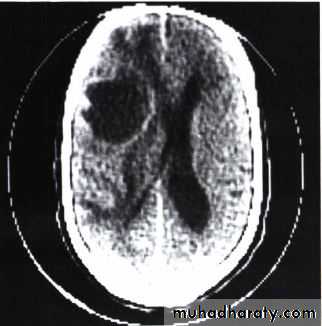

LUNG CANCER - Dr. Mustafa Nema- Baghdad College of Medicine3) Metastasis

Symptoms occur due to blood-borne metastases. The most frequent sites of distant metastasis are the:• liver: (pain, jaundice, constitutional symptoms).

• brain: (headache, paresis, personality change, seizures)

Brain metastasis